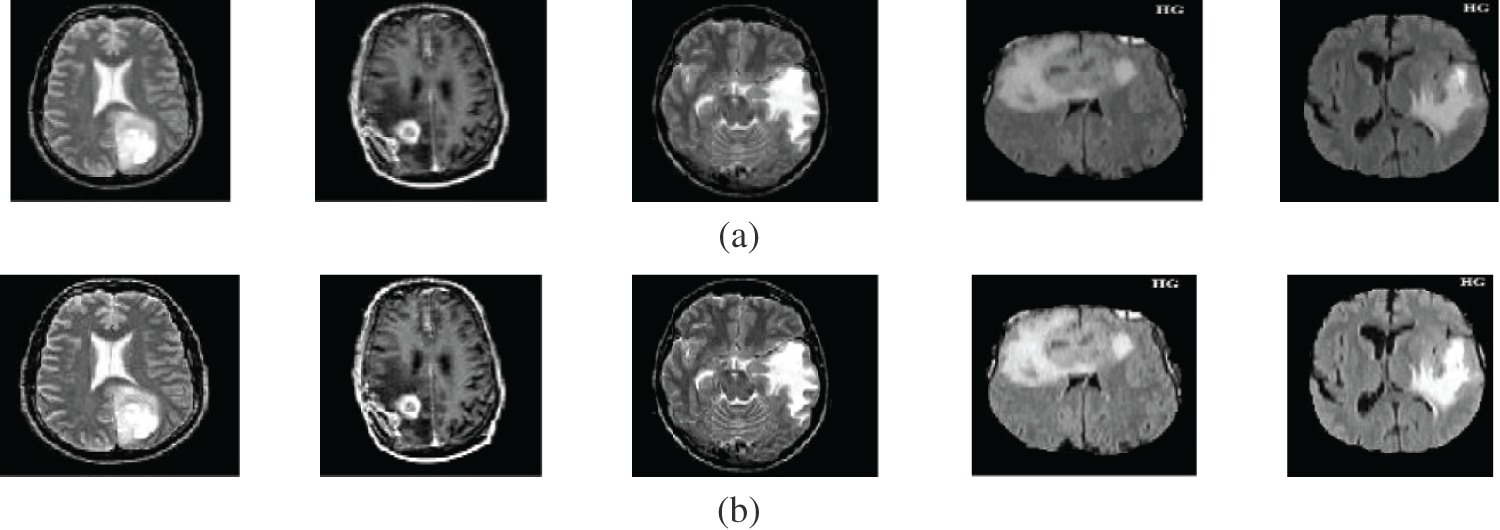

Fig. 5a shows samples of the PET brain images, Fig. 5b shows the PET images after pre-processing stage, Fig. 5c shows the FCM and morphological stage output images, Fig. 5d shows the segmentation results of the ROI produced by active contour model, and Fig. 5e shows the resultant ROI images. Fig. 6a shows samples of the MRI brain images, Fig. 6b shows the MRI images after pre-processing stage, Fig. 6c shows the FCM and morphological stage output images, Fig. 6d shows the segmentation results of the ROI produced by active contour model, and Fig. 6e shows the resultant ROI images. Tabs. 1–5 show the segmentation Accuracy (Acc.), Sensitivity (Sens.), Precision (Pr.), F-Measure (FM), Matthews Correlation Coefficient (MCC), Dice (D), Jaccard (J), and Specificity (Spec.) numerical results on different image modalities.

Figure 6: A sample of the MR medical images (a) MR images, (b) MR images after preprocessing stage, (c) FCM and morphological operation output images, (d) Segmented images after active contour, and (e) The extracted tumor images

Fig. 6 gives the results of the proposed segmentation approach applied to the MRI brain images. As shown in Fig. 6b, the enhancement results considerably enhance and improve the image contrast. The results of the morphological operations and FCM, shown in Fig. 6c, splits the images into sub-regions as shown in Fig. 6d. Finally, the proposed approach extracts the tumors in each image, as shown in Fig. 6e. The segmentation metrics for the MRI brain images are given in Tab. 6, and the obtained average segmentation accuracy is 0.9978. The proposed approach shows excellent performance for delineating and extracting the tumor boundaries with good quantitative and qualitative results.